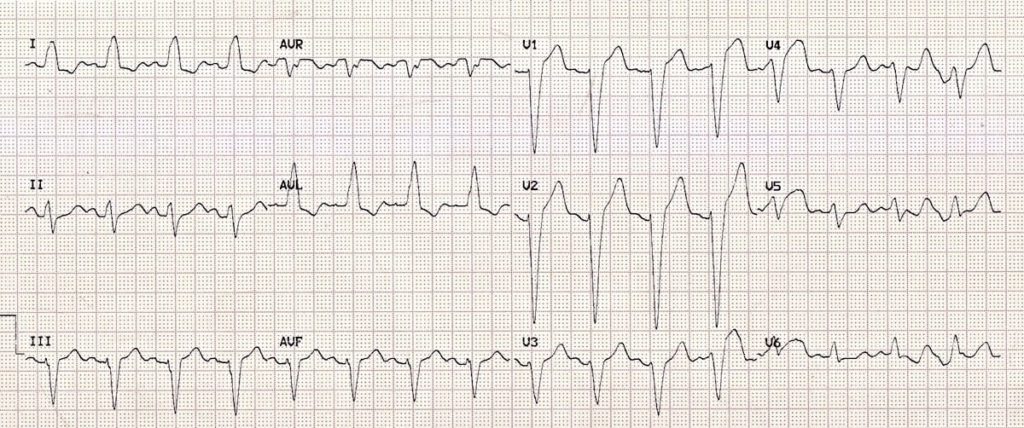

This ECG shows left axis deviation. Applying the thumb rule: lead I is up (+ve) and lead aVF is down (-ve). The left axis deviation is secondary to left ventricular hypertrophy.

© Life in the Fast Lane. Licensed under CC BY-NC 4.0

This ECG shows right axis deviation. Applying the thumb rule: lead I is down (-ve) and lead aVF is up (+ve). The right axis deviation is secondary to right ventricular hypertrophy (from cor pulmonale).

https://litfl.com/top-100-ecg-cases/

© Life in the Fast Lane. Licensed under CC BY-NC 4.0